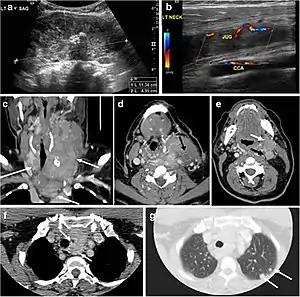

A goiter is an abnormal thyroid gland proliferation that manifests as multi-nodular, uni-nodular, or non-nodular diffuse glandular enlargement. A goiter is formed of solid matrix, colloid cysts, blood products, calcification, and fibrosis, and this heterogeneity may lead to variable appearances on a CT scan (Figs. 13, 1414 and and15)15). The US is more sensitive in evaluating thyroid nodules within a goiter; however, a symptomatic goiter may require surgical treatment with total thyroidectomy, and in this case CT plays an additional role in preoperative evaluation. Specific aspects for examination on a CT scan during the preoperative evaluation for goiter include extension, mass effect, and suspicious features of malignancy.[1]

Fig. 13. A 27-year-old female patient known to have goiter. a, b Axial and sagittal enhanced CT scan images of the neck demonstrate a heterogeneously enhancing, enlarged thyroid gland with scattered calcifications (white arrow), cystic changes, and substantial retro-sternal extension (black asterisks). No lymphadenopathy or substantial airway narrowing.[1]

Fig. 14. A 19-year-old male patient known to have multi-nodular goiter and FNA, showing underlying Hashimoto's thyroiditis. a, b Sagittal and transverse greyscale and colour Doppler ultrasound of the neck demonstrate a hypoechoic enlarged right thyroid lobe with small hyperechoic regenerative nodules and marked hypervascularity (white arrows). c, d Enhanced axial CT scan images of the neck demonstrate a heterogeneously enhancing and enlarged thyroid gland, left more than right lobe, and the trachea is markedly narrowed.[1]

Fig. 15. A 33-year-old female patient who presented with neck swelling and pain and was later diagnosed with Hashimoto's thyroiditis. an Axial enhanced CT scan of the neck demonstrates minimal diffuse enlargement of the thyroid gland, especially the isthmus (white arrow). b Transverse greyscale ultrasound of the neck demonstrates heterogeneously enlarged thyroid and thickened isthmus, measuring 8.6 mm.[1]

Malignancy can coexist within the goiter and a CT scan may give a clue if there are abnormal cervical lymph nodes and/or signs of invasion. Retrosternal extension (Fig. 15) could affect the surgical approach, as a lower extent may require a partial or total sternotomy to facilitate complete resection. Therefore, the distance of the retrosternal extent from the sternal notch should be measured on a sagittal image.[1]

The interpreting radiologist should describe the mass effect, detailing its degree and direction of displacement of central structures, including the trachea, oesophagus, larynx, and pharynx. Attention should be directed to the upper extent of the goiter and structures immediately surrounding the thyroid gland, including the neuro-vascular structures, retropharyngeal space, and pre-vertebral space. The reporting radiologist should evaluate the vocal cords for symmetry and signs of vocal cord palsy.[1]